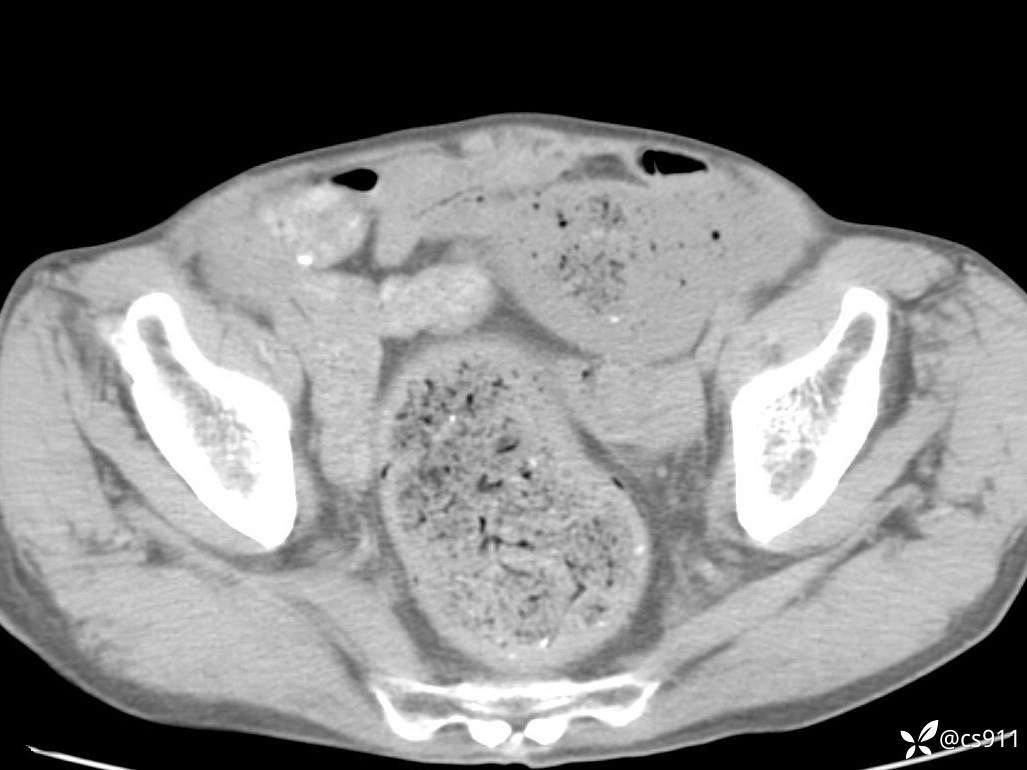

急腹症之急诊CT,原因?答案公布

男,77岁,腹痛、腹胀伴恶心呕吐1天。呕吐胃内容物,非喷射性呕吐,有咖啡色样胃内容物,诉有胃穿孔病史。查体:全腹平,下腹部压痛,全腹无反跳痛,叩诊呈浊音,移动性浊音阴性,肠鸣音减弱,1-2次/分。肛检:直肠未扪及明显肿物,可触及大量粪块。